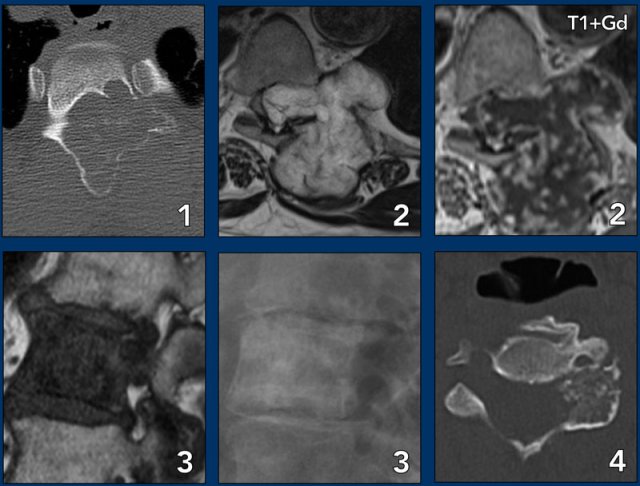

Spine lesions

Here some typical examples of bone tumors in the spine.

- Hemangioma.

- Metastasis.

- Multiple myeloma.

- Plasmocytoma: vertebra plana.

This 'Mini Brain' appearance of plasmacytoma in the spine is sufficiently pathognomonic to obviate biopsy (9).

More examples

- ABC

- Chondrosarcoma

- Metastasis of breast cancer

- Osteoblastoma